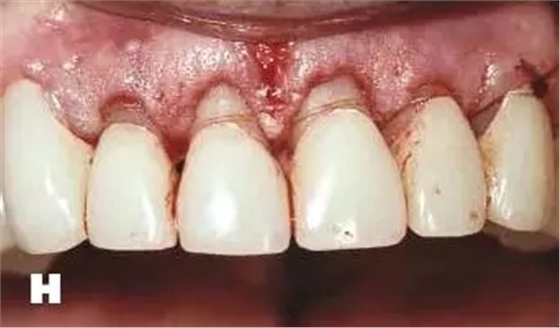

牙周炎發(fā)展到一定階段時(shí),僅采用基礎(chǔ)治療難以取得較好療效,必須通過(guò)適時(shí)而合宜的手術(shù)治療挽救患牙,才能保持牙周組織健康,延長(zhǎng)患牙在口腔內(nèi)的壽命,維持牙列的完整性,促進(jìn)全身健康。其手段包括齦下刮治、根面平整、牙周翻瓣術(shù)、牙齦切除術(shù)、牙周夾板固定術(shù)等。